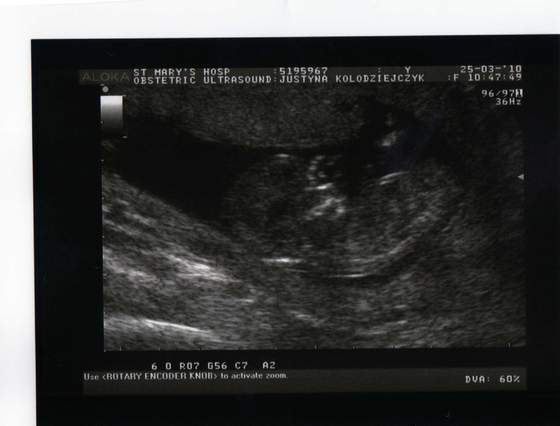

a to moj maluszek w 12 tygodniu :-)

Załączniki

• img013..jpg

img013..jpg

19,8 KB · Wyświetleń: 117